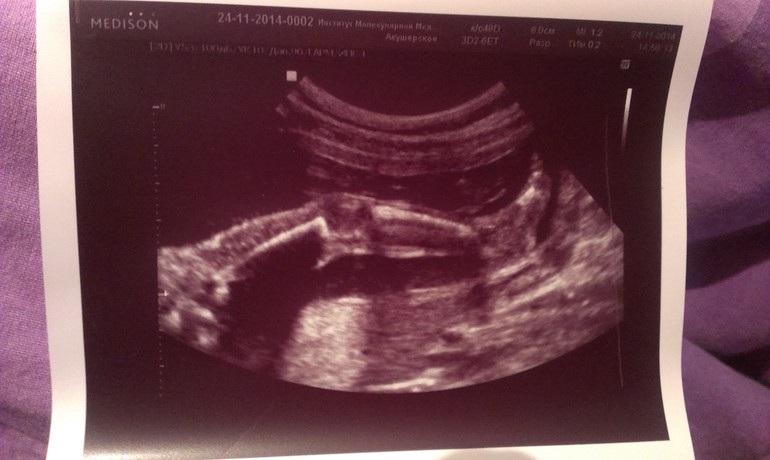

Второе плановое узи! 21 + 1, фото :)))

Наконец наша вторая плановая встреча с малюткой! Все отлично, все органы в порядке, лежит головкой вниз, размеры крошки соответствуют сроку, она наша умничка! Сегодня показывала как она умеет сладко зевать и какие у нас красивые маленькие стройные и женственные ножки.

И в заключение - фото пузика на отдыхе и нашей сладкой и так активно демонстрируемой сегодня ножки